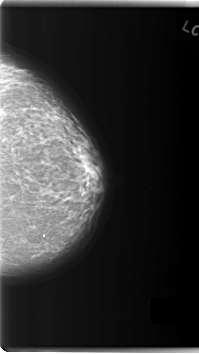

C_0183_1.LEFT_MLO

LEFT_MLO LINES 5968 PIXELS_PER_LINE 3416 BITS_PER_PIXEL 12 RESOLUTION 50 NON_OVERLAY